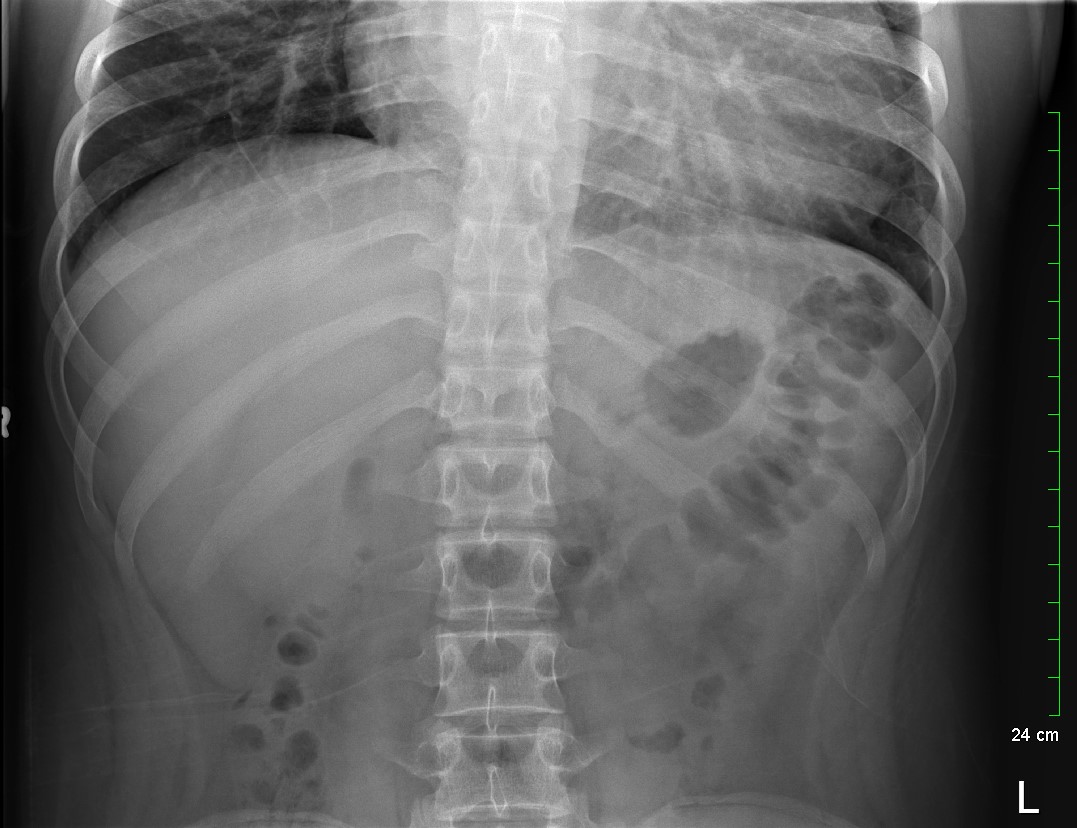

Because the patient presented with prolonged vomiting, a complete blood count (CBC), comprehensive metabolic panel (CMP), lipase, and kidney, ureter and bladder (KUB) was obtained. Initial labs showed only mild transaminitis and metabolic acidosis (AST 106, ALT 188, HCO3 15). KUB revealed the following images:

Subsequent workup

KUB read as normal by radiology. However, because of the enlarged heart border found incidentally on KUB, troponin I (0.05 ng/mL), B-type natriuretic peptide (BNP) (2186 pg/mL), and chest x-ray (CXR) was obtained, which showed the following: